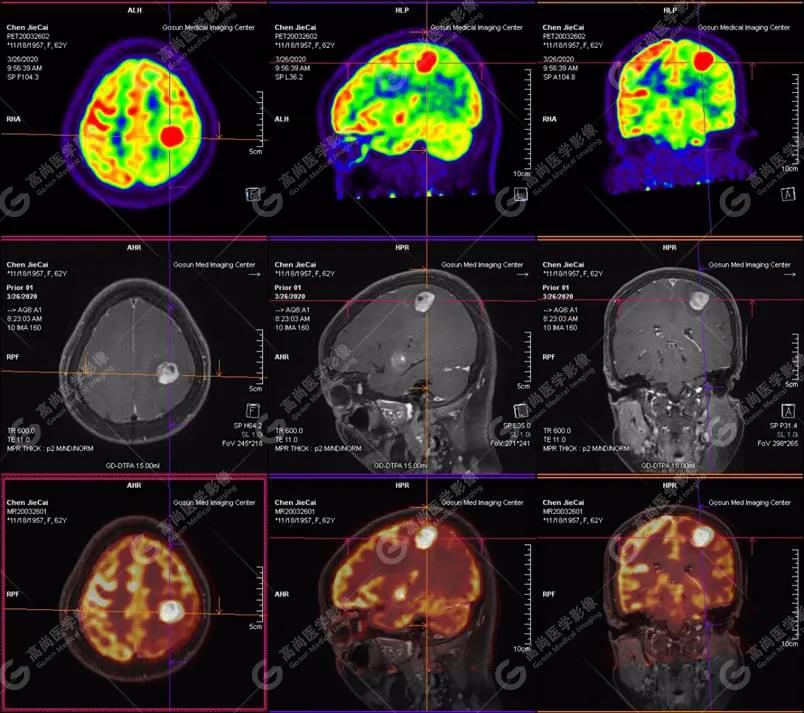

【廣東高尚醫(yī)學(xué)影像】多模態(tài)影像|顱內(nèi)淋巴瘤PET-MR融合顯像1例

影像圖

PET-MR融合診斷

左側(cè)顳葉、頂葉、左側(cè)基底節(jié)區(qū)及胼胝體部多發(fā)結(jié)節(jié)狀高代謝病灶,部分合并囊變、出血,MR平掃+增強(qiáng)示不均勻輕、中度強(qiáng)化,綜合考慮為顱內(nèi)原發(fā)惡性腫瘤,以淋巴瘤可能性大

18F-FDG PET PET顯像中呈明顯高代謝病灶。

顱內(nèi)惡性淋巴瘤對(duì)18F-FDG的攝取率很高,一般SUV在5~10以上,18F-FDG PET顯像中攝取明顯高于正常腦皮層,因此具有特征性。